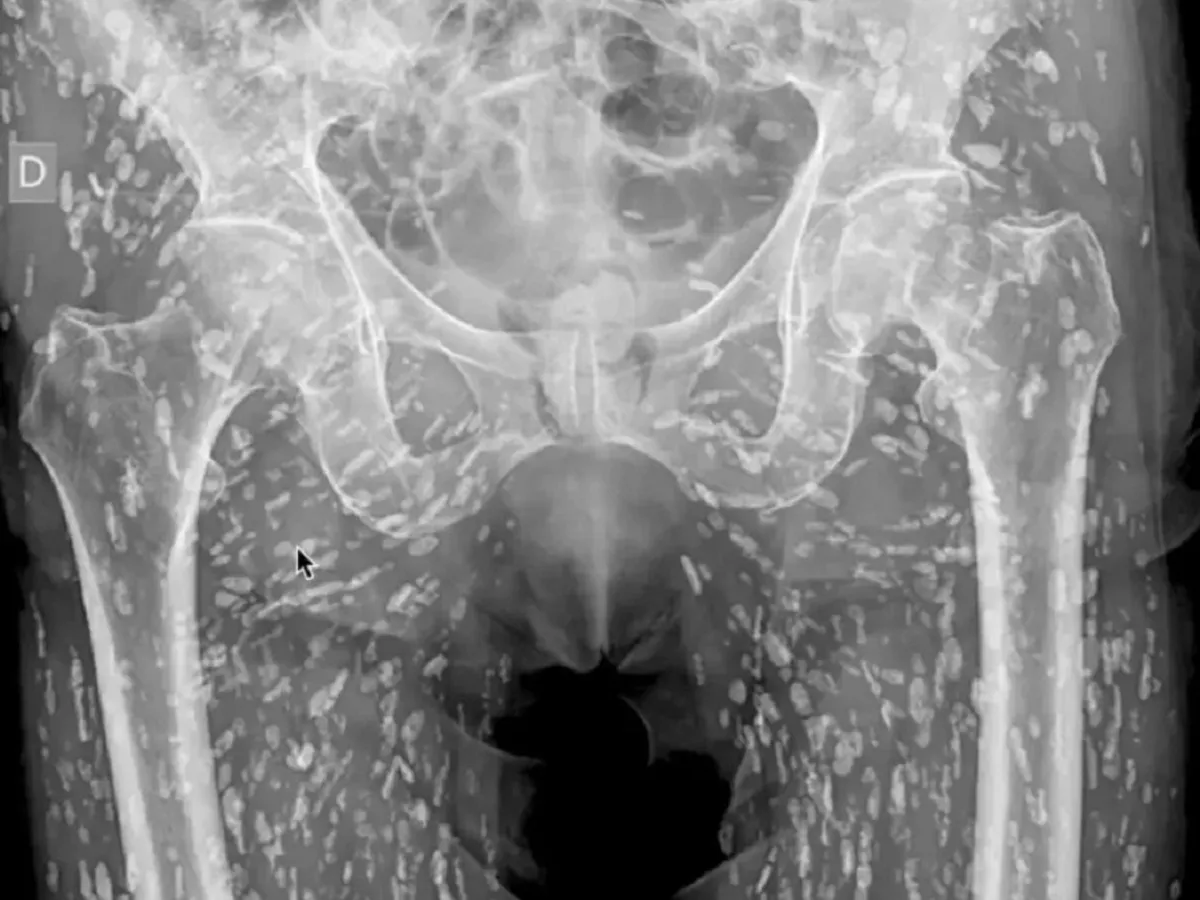

Sam Ghali, medic de urgență specializat în urgențe cardiovasculare și radiologie de urgență la Clinică medicală din Jacksonville, Florida, a împărtășit recent o radiografie neobișnuită a zonei pelvine a unui pacient care arăta corpul acestuia plin de sute de pete albe.

„Este una dintre cele mai nebunești radiografii pe care le-am văzut vreodată”, a spus Ghali, după ce a analizat partea inferioară a corpului unei persoane infestată cu sute de ouă de tenie calcificate, scrie odditycentral.com.

Acestea rămăseseră blocate în țesuturile moi din partea inferioară a corpului său. Interesant este că pacientul nu a știut niciodată despre cisticercoza sa și a aflat abia când s-a prezentat pentru o radiografie după ce a căzut și a acuzat dureri la șold.

Radiografia arată zona pelviană a pacientului infestată cu ouă calcificate de tenie - Foto: captură X

În timp, aceste ouă se calcifică și nu mai sunt viabile, astfel încât nu reprezintă o amenințare prea mare atunci când se depozitează în țesuturile moi, cum ar fi mușchii sau grăsimea, dar pot provoca o afecțiune care pune viața în pericol, cunoscută sub numele de neurocisticercoză, atunci când se calcifică în creier.

„Aceasta este o afecțiune cunoscută sub numele de cisticercoză, în esență acestea sunt chisturi larvare de taenia solium, cunoscută și sub numele de „tenia porcului”.

Aceste chisturi se pot deplasa oriunde în întregul corp, cu precădere la nivelul țesuturilor musculare și moi ale șoldurilor și picioarelor”, a explicat Ghali pe platforma X (Twitter), care a postat și un clip cu radiografia respectivă, pe care-l puteți vedea mai jos.